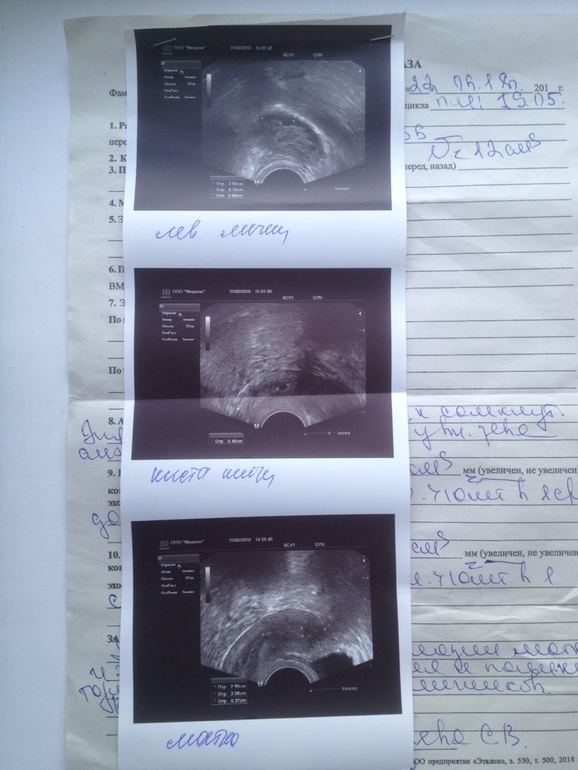

В апреле не пошли месячные, пошла к гинекологу назначил Дюфастон, месячные пошли 19 мая, сейчас июнь и опять пять дней задержки, тест на беременность и снова отрицательный, пошла на прием уже к другому гинекологу (платному) в частный медицинский центр, она взяла мазки, отправила на УЗИ, поставили диагноз гипоплазия матки и эндометрия, увеличение и поликистоз обоих яичников, врач сказала, что с таким диагнозом о детях могу и не мечтать, пока не вылечусь. Назначила мне прогестерон колоть чтобы вызвать месячные и сдать анализы на половые гормоны, написала она их 8, а это по 2 тысячи рублей каждый, стоит ли сдавать эти тесты, может какие либо другие есть способы лечения?